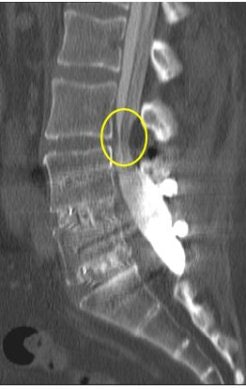

| Above, midsagittal T2-weighted MRI showed increase in stenosis at the L4 level by 2.0 mm with ventral thecal sac compression with axial loading (below). All images courtesy of Dr. Gerald Anzalone. |

| Increased conspicuity of L4-L5 disk bulge and 2.0 mm increase in stenosis at the L4-L5 level with axial loading. |